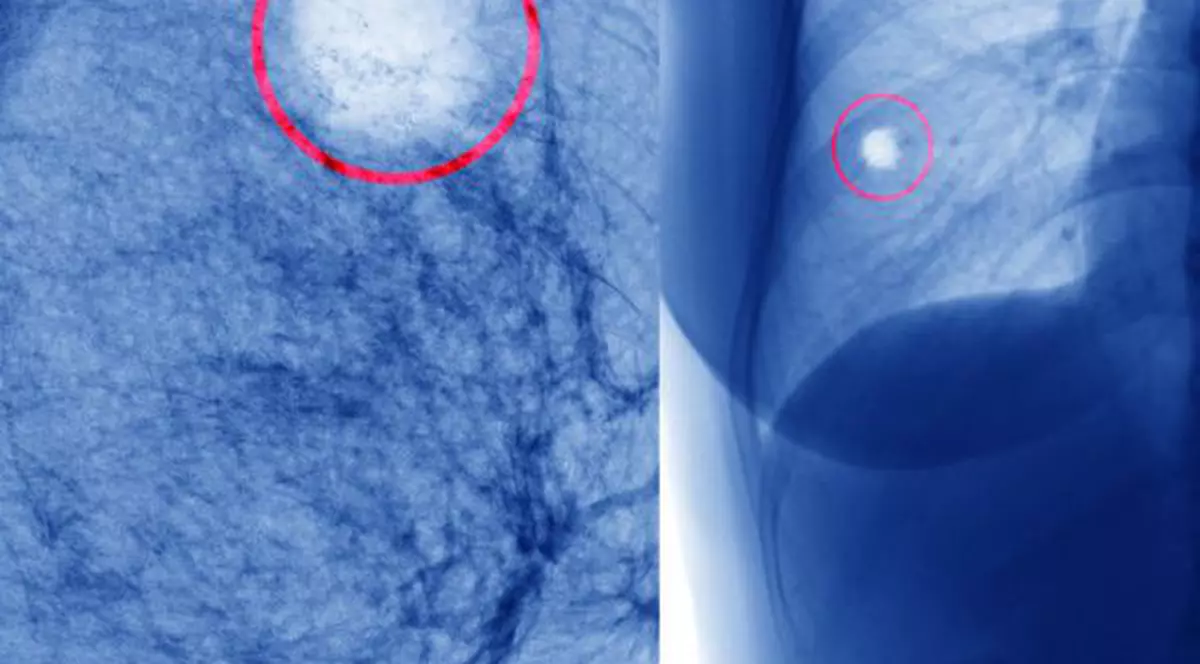

Riscul de cancer colorectal este legat în proporție de 75 la sută de dietă, cel de cancer de piele, în proporție de 86 la sută de expunerea la soare, în timp ce cancerul în gât sau a nivelul capului este legat de tutun și alcool în proporție de 75 la sută. Concluzia este că îmbolnăvirile de cancer ar scădea cu 70-90 la sută dacă am exclude din viața noastră factorii de risc.